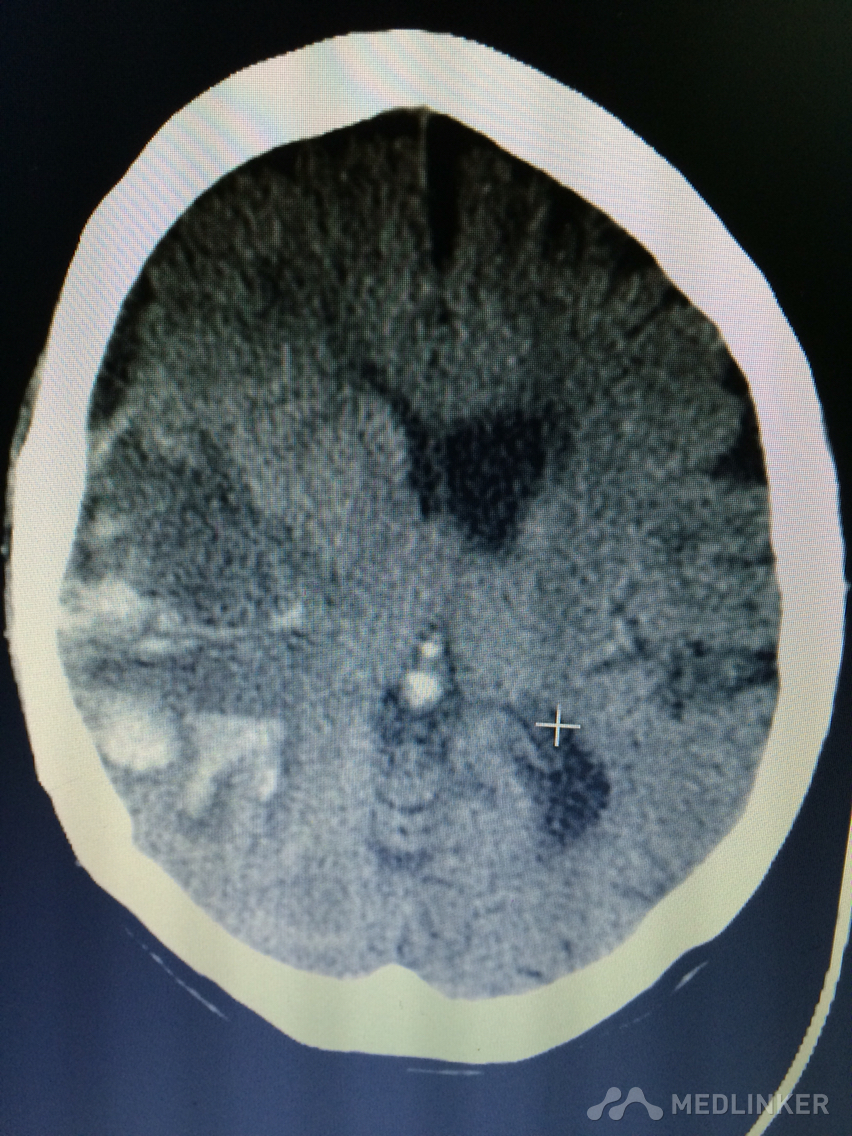

下面的CT考虑?

1天前,患者睡醒后出现反应迟钝,认知功能障碍,左侧肢体乏力。 既往无高血压病史,近期无外伤史。